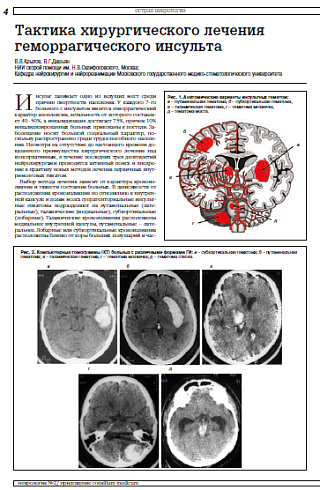

Тактика хирургического лечения геморрагического инсульта

В.В.Крылов, В.Г.Дашьян. Тактика хирургического лечения геморрагического инсульта. Consilium Medicum. Неврология (Прил.). 2009; 2: 4-9.